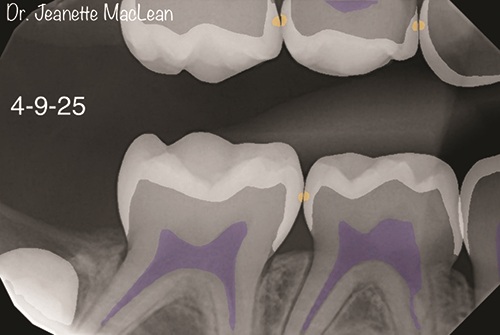

Fg2a_DT1225_MacLean_30616

Icon Smooth Surface Case Study by Jeanette MacLean, DDS